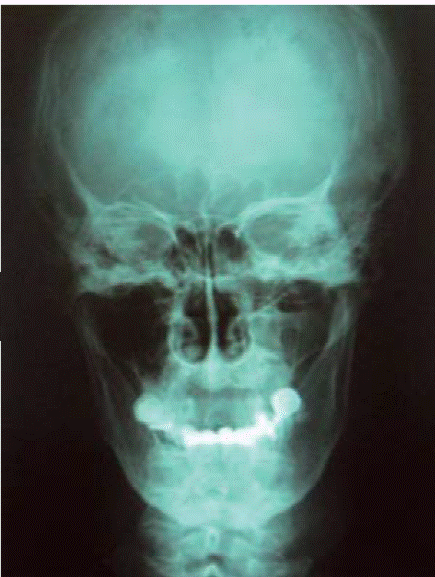

El resultado histopatológico reportó necrosis focal con inflamación crónica y aguda ulcerada asociada con microorganismos morfologicamente compatibles con Actinomyces, compatible con osteomielitis aguda y crónica, el gammagrama óseo reportó aumento del recambio celular compatible con inflamación y en las imágenes radiográficas de la ortopantomografía y la anteroposterior de cráneo (Figuras 2y3) se observa lesión invasiva a seno maxilar derecho (Cuadro I).

Figura 3 Proyección radiográfica anteroposterior donde se observa la gran pérdida ósea en maxilar derecho.